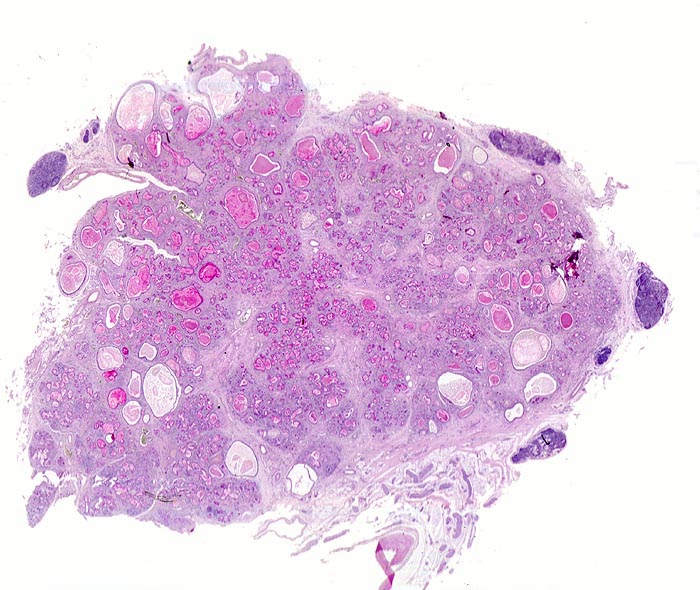

Mucoviszidose

Pankreas

Neben einer mässig ausgeprägten Fibrose fallen in der Übersicht vor allem die zahlreichen dilatierten und mit eingedicktem PAS positivem Schleim angefüllten Gänge auf. Die dunkelblauen Knoten im peripankreatischen Gewebe entsprechen dort üblicherweise vorhandenem lymphatischem Gewebe.

Der Patient verstarb an einer Pneumonie. Es bestand eine Insuffizienz des exokrinen Pankreas mit Malabsorption.